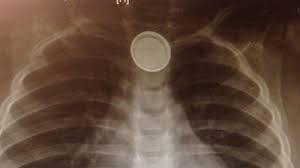

Nam thanh niêm bị thủng 5 lỗ ruột non do nuốt chửng 2 cọng kẽm

Nam thanh niên bị thủng 5 lỗ tại ruột non do nuốt phải 2 cọng kẽm, mỗi cọng dài 5 cm. Bác sĩ cho biết, nếu không phẫu thuật để lấy cọng kẽm ra kịp thời ruột non sẽ bị hoại tử nhanh chóng.

Trẻ có thể tử vong do... pin cúc áo

Ống tiêu hóa của trẻ còn quá nhỏ, nên khi nuốt, pin sẽ mắc lại ở thực quản. Lúc này, sự tiếp xúc của cục pin với nước bọt, dịch tiêu hóa sẽ tạo nên một dòng điện gây bỏng ở thực quản và ống tiêu hóa. Nghiêm trọng hơn, nó có thể tiếp tục đốt cháy mạch máu lớn dẫn tới hiện tượng chảy máu, đe dọa đến tính mạng.